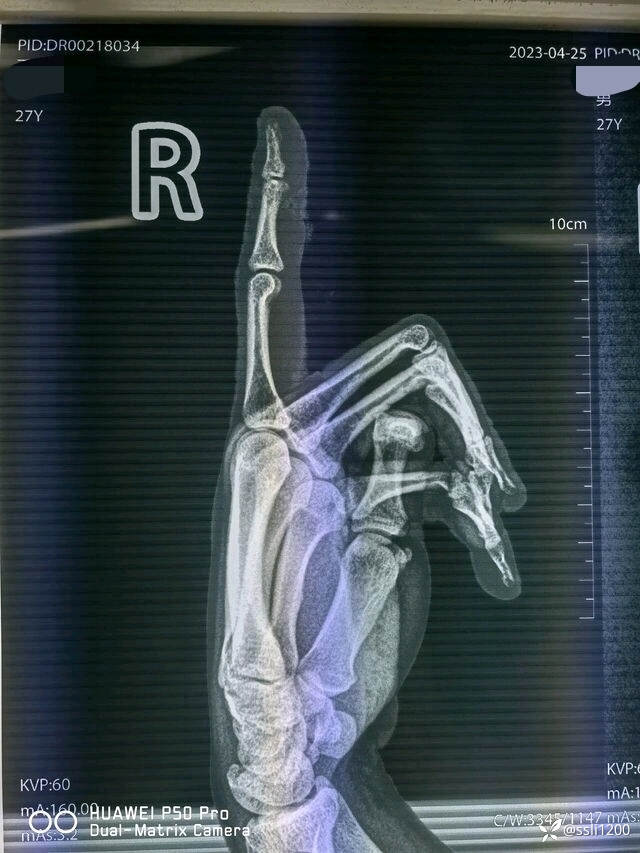

辅助检查:2023-04-25 本院DR检查提示:右示指骨质未见明显异常。

术前DR